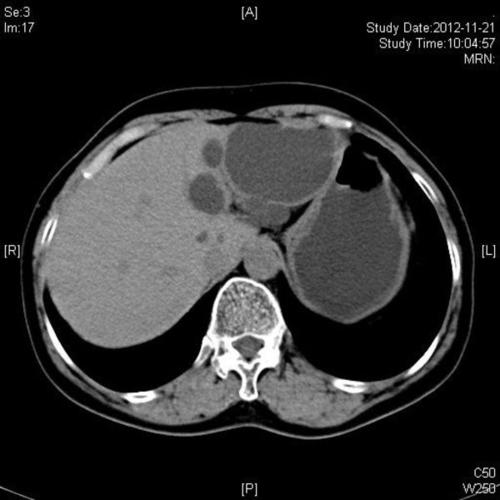

肝囊肿ct图片报告,肝囊肿ct图片

要求给予治疗,从ct检查来看,肝内多发囊肿,最大者左右肝各一12cm直径

(付女士ct检查,左显示乳腺癌术后肝转移瘤,右显示肝囊肿)

肝囊肿ct图(2)(2/5)